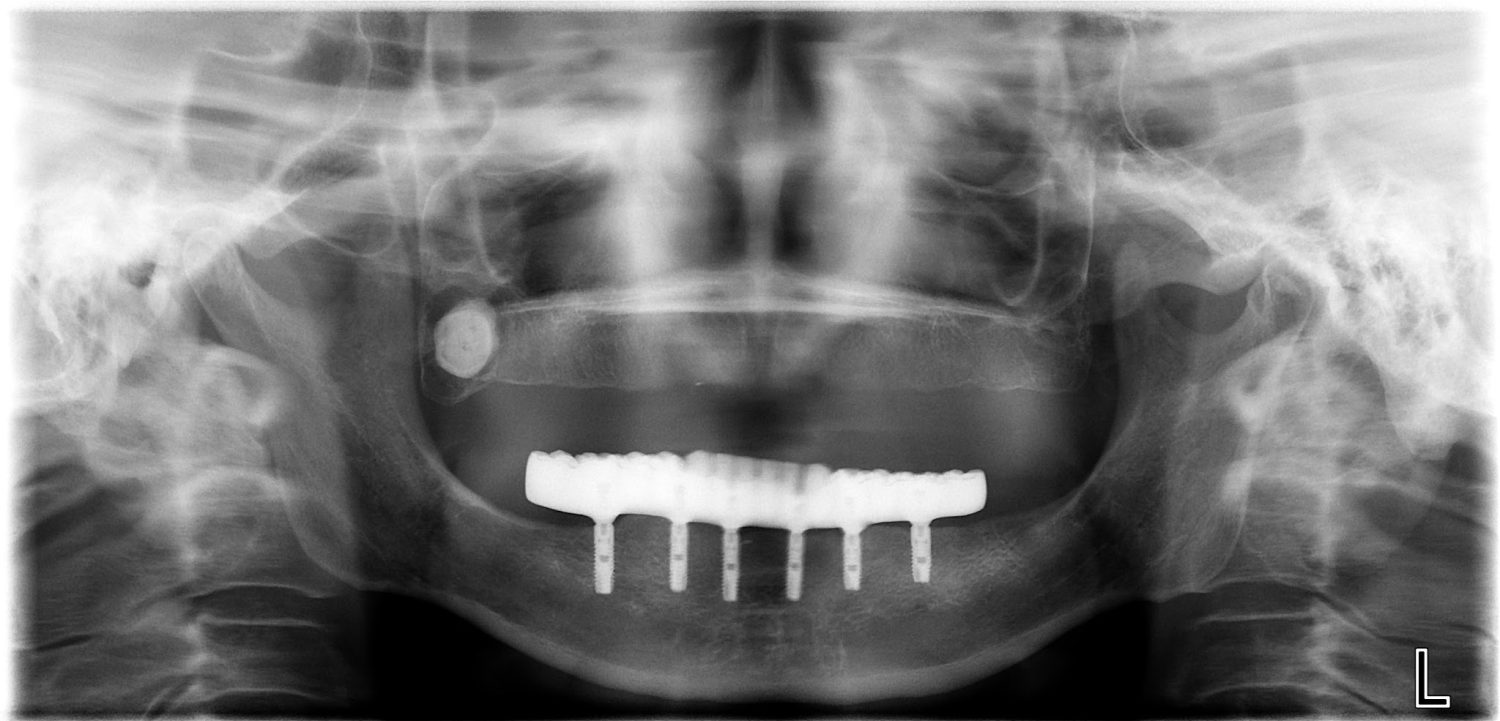

インプラント治療の症例紹介③

Before

After

治療内容

保存不可能な歯の抜歯

下顎にインプラント埋入し咬合再構成

多数歯う蝕および多数歯欠損による咬合崩壊、保存不可能な歯の抜歯により上下無歯顎に。下顎に6本インプラント埋入する事で咬合再構成を行った。